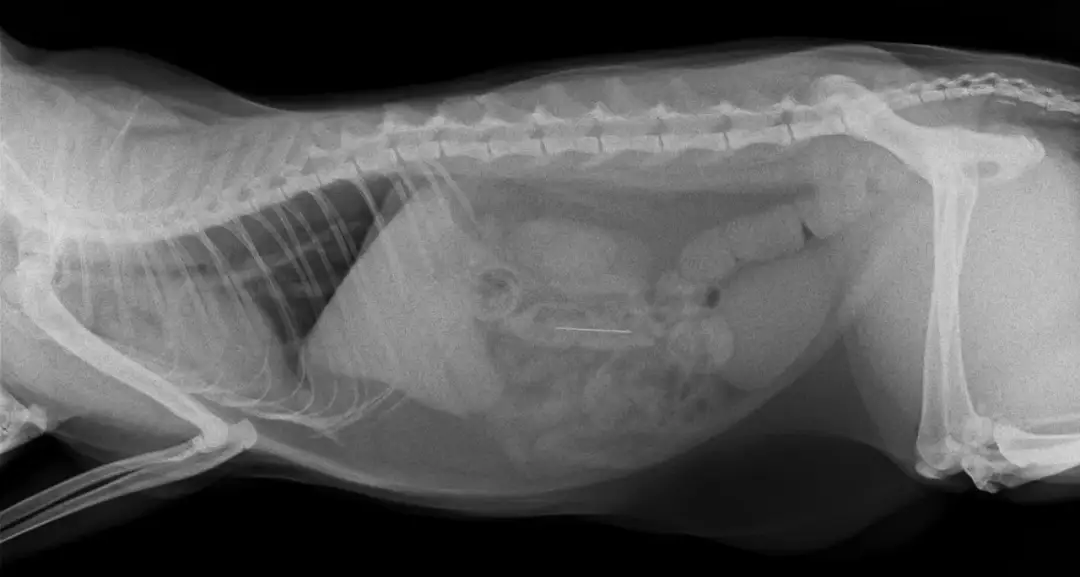

Pies połknął ciało obce? Sprawdź, kiedy pojawią się objawy i jak szybko reagować, by uratować jego życie. Nie ryzykuj, działaj!